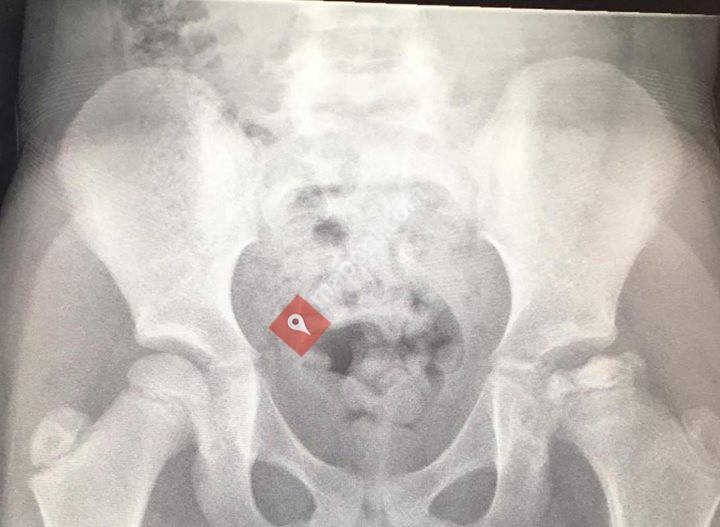

Ik schrijf over mijn dochter van 6, zij heeft de kinderziekte van Perthes. Op internet kan ik er niet veel over vinden, daarom delen wij onze ervaringen.